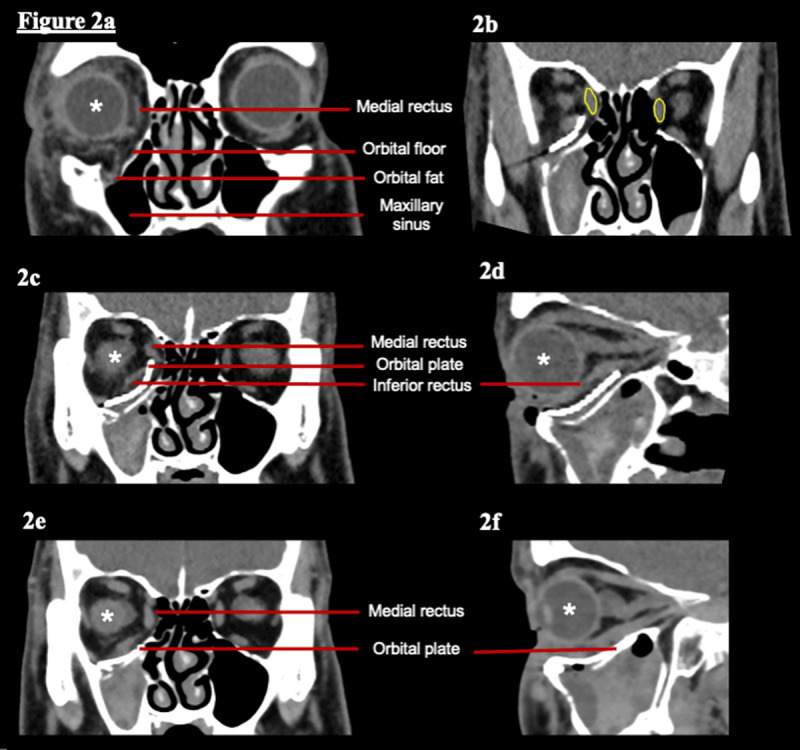

我们描述了一个罕见的病例回旋扭转可能继发于内侧直肌和下直肌病理的病人眼眶外伤。包括赫斯图在内的顺序正视测量与患者治疗过程中眼眶CT扫描的相关部分一起呈现。在植入钢板修复眶底骨折后,患者出现旋回扭转。顺序的正视评估和成像相结合的方法揭示了可能的潜在机制。下直肌机械限制加上内侧直肌滑轮的移位似乎是可能的罪魁祸首。一旦将眶钢板换成较小尺寸的钢板,患者的症状和临床特征就会消失。虽然眶板错位并不罕见,但内侧直肌偏曲是引起旋回扭转的原因,以前没有报道过。我们将讨论具有相似正视检查结果的患者的替代差异以及如何将其排除在外。

We describe a rare case of cyclotorsion likely secondary to medial rectus and inferior rectus pathology in a patient with orbital trauma. Sequential orthoptic measurements including Hess charts are presented alongside relevant sections of the orbital CT scans over the course of the patient's treatment. Following the insertion of a plate to repair an orbital floor fracture, the patient developed cyclotorsion. A combined approach of sequential orthoptic assessment and imaging revealed the likely underlying mechanism. Inferior rectus mechanical restriction combined with displacement of the medial rectus pulley appear to be the likely culprits. Once the orbital plate was exchanged for a smaller sized plate the patient's symptoms and clinical features resolved. Although orbital plate malpositioning is not an uncommon event, medial rectus deviation as a cause of cyclotorsion has not previously been described. We discuss the alternative differentials for patients with similar orthoptic findings and how they were excluded.